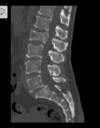

Fratura compressiva da coluna lombar

Causa achatamento do corpo e acunhamento geralmente anterior.

Tipo mais comum de fratura da coluna lombar

Estável.

Mecanismo flexão anterior ou lateral